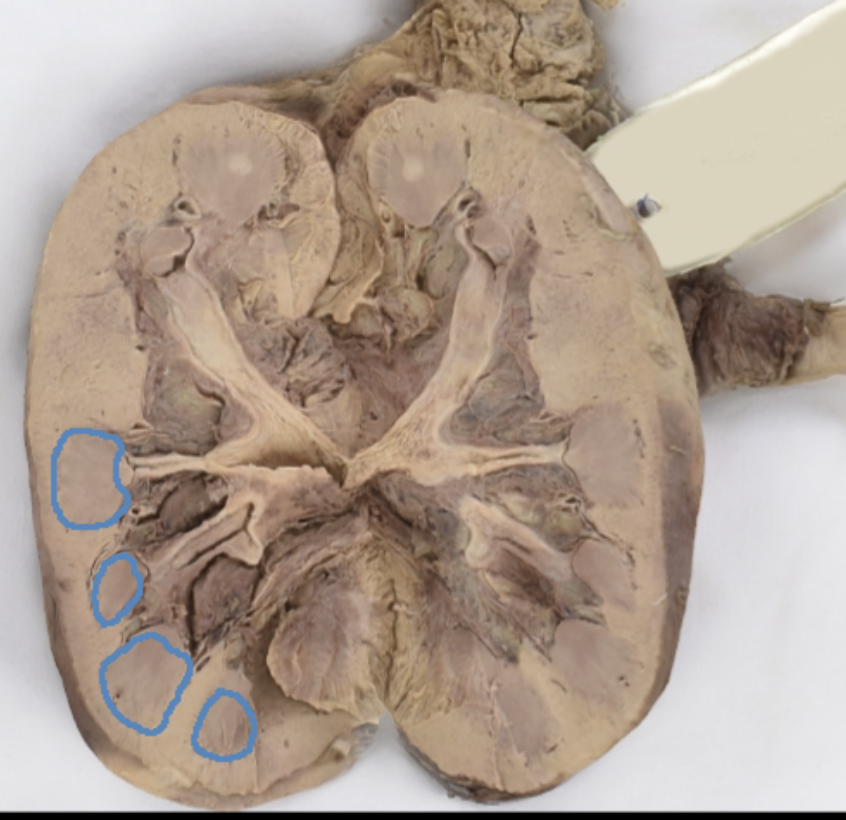

renal cortex

green

renal medulla

blue

renal columns

yellow

renal pyramids

purple

renal lobe

orange

renal papilla

minor calyx

teal

major calyces

renal pelvis

minor and major calyces